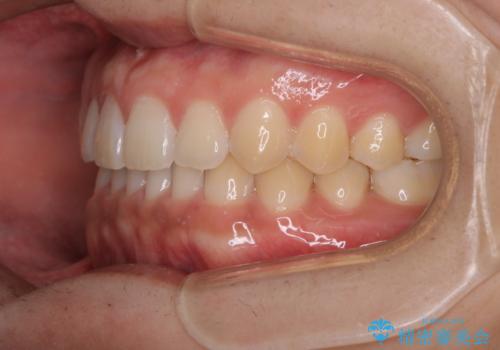

- 上のすきっ歯が気になるとご相談にいらした方です。上下顎ともにスペースがあったため、インビザラインFULLにて見た目と噛み合わせの改善も同時に行いました。

元々は上前歯のみの部分矯正をご希望されていましたが、下の歯もスペースがあり、噛み合わせ的にも上のみの部分治療は難しいことをお話ししました。前歯のみの部分矯正を行った場合、前歯の隙間だけが閉じて奥歯が噛めなくなってしまう場合もあります。インビザラインFULLにて治療することで、噛み合わせと見た目を同時に改善させることができ、大変喜んでいただけました。